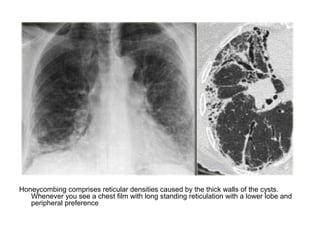

Honeycombing comprises reticular densities caused by the thick walls of the cysts.

Whenever you see a chest film with long standing reticulation with a lower lobe and

peripheral preference